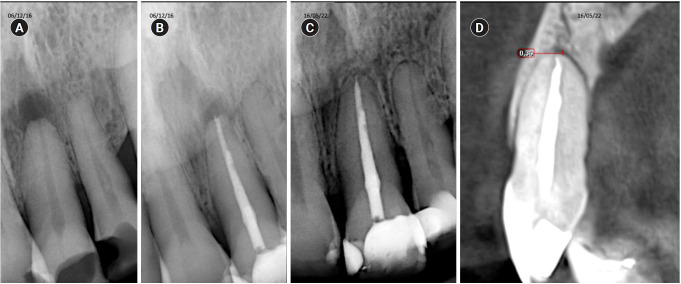

Methods: Teeth with apical lesions underwent endodontic treatment in which a high-power 810-nm diode laser with saline solution was used as monotherapy for disinfection. This type of therapy aimed to replace the traditional irrigation protocol with sodium hypochlorite. This research is the first to assess the clinical success of this alternative treatment, along with tomographic evaluations conducted over periods ranging from 2 to 7 years, analyzed using the periapical index based on cone-beam computed tomography (CBCTPAI). All cases were performed by a single clinician following the same laser protocol, which involved using 1 W of continuous power and four cycles of 20 seconds of laser activation.

Results: All teeth showed no clinical symptoms upon follow-up examination. However, the tomographic evaluation revealed that the success rates for teeth receiving primary treatment were 60% and 80% according to strict and loose criteria, respectively. For teeth requiring retreatment, the success rates were 12.5% and 37.5% using strict and loose criteria, respectively.

Conclusions: The teeth with apical lesions that underwent primary treatment did not present clinical symptoms, but they showed a moderate success rate on tomographic evaluation. However, despite lacking clinical symptoms, teeth with apical lesions that required retreatment had a very low success rate on tomographic evaluation.